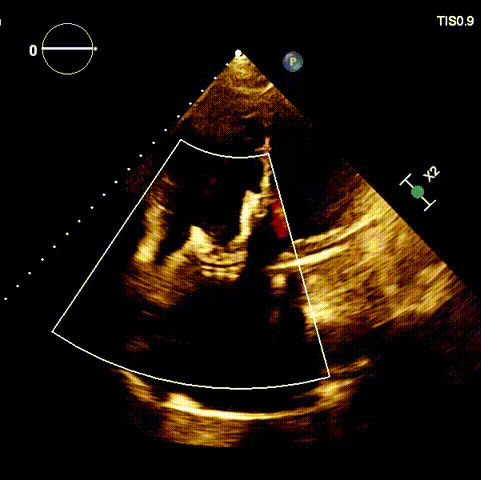

術(shù)后超聲

近日,廈門大學(xué)心血管病醫(yī)院王焱教授帶領(lǐng)的結(jié)構(gòu)性心臟病團(tuán)隊,成功應(yīng)用LuX-Valve Plus經(jīng)血管三尖瓣置換系統(tǒng),為一例高危三尖瓣重度反流患者開展經(jīng)血管三尖瓣置換手術(shù)。此次手術(shù)系LuX-Valve Plus人工瓣膜在福建省的首例植入,手術(shù)過程順利,術(shù)后患者三尖瓣反流顯著改善,標(biāo)志著由葛均波院士團(tuán)隊作為主要研究者的LuX-Valve Plus經(jīng)血管三尖瓣置換系統(tǒng)全國多中心臨床研究的再一次成功實(shí)踐,為三尖瓣介入治療的醫(yī)學(xué)循證打下了夯實(shí)的基礎(chǔ)。 、